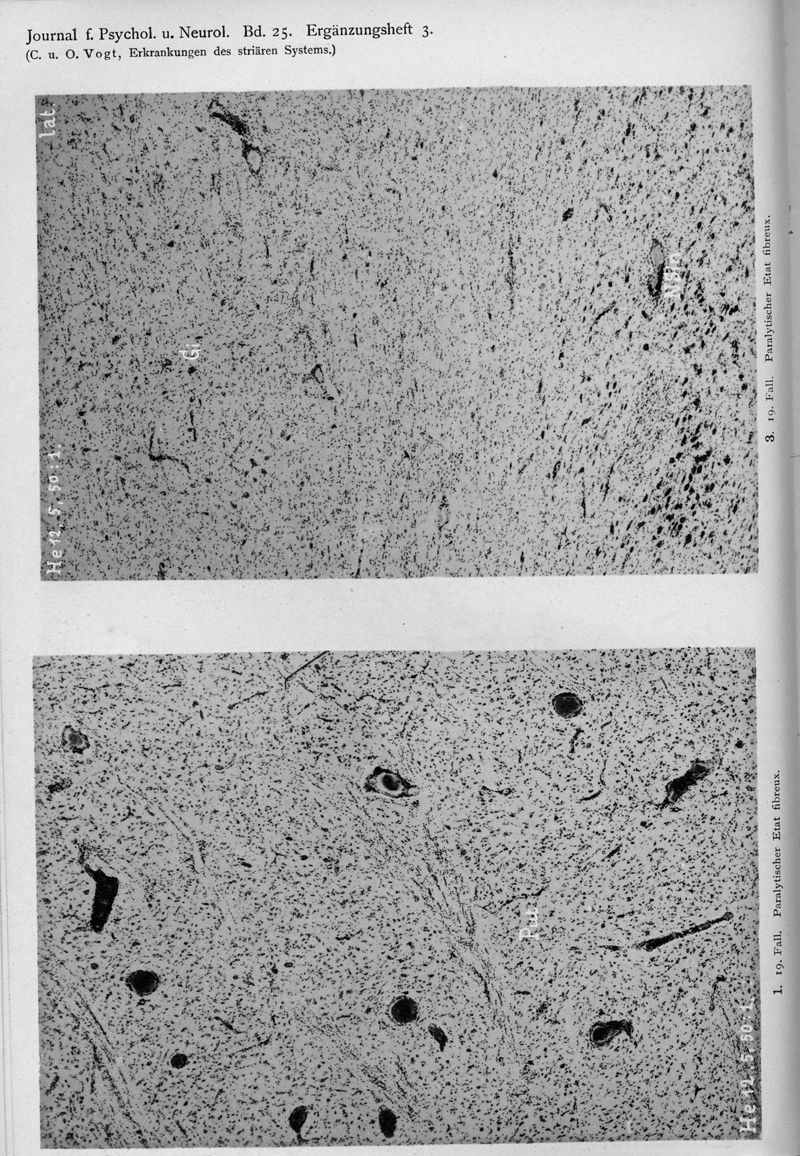

VOGT, Cécile / VOGT, O.

In : Journal für Psychologie und Neurologie,

1920, Vol. 25, pp. 627-846